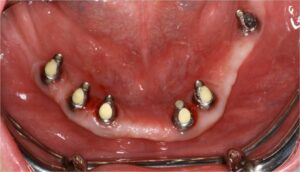

- Προσθετικη επι εμφυτευματων